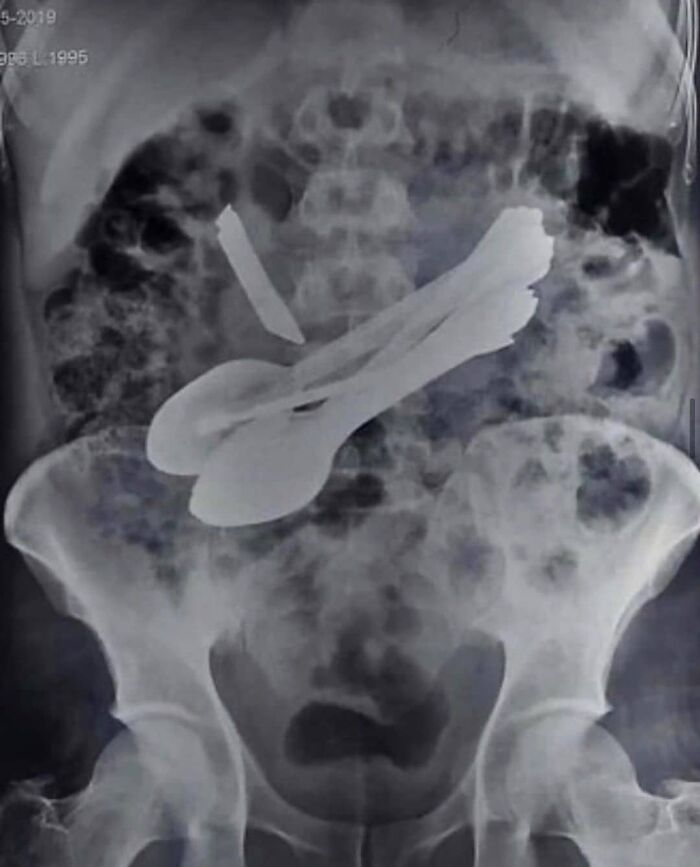

#92 X-Ray Photo Of A Patient Who Swallowed Spoons, Scewdrivers, Tootbrushes And A Knife!

A condition called acuphagia. This person SWALLOWED 2 screwdrivers, 2 toothbrushes, 8 spoons and a kitchen knife!! After a 4 hour surgery, all of the items were removed from his stomach(second picture) and he made a full recovery. Acuphagia is described as eating sharp metal objects and is recognised as a type of pica. Basically, pica refers to eating non-nutritive, non-food items in people without any underlying mental disorders. Pica is most commonly seen in pregnant women, small children and those with psychiatric disorders (developmental disorders, autism spectrum disorder, and even schizophrenia).